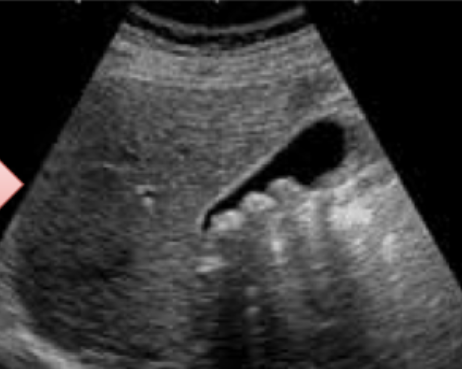

An ultrasound image from a patient with recurrent upper abdominal pain.

Q1: What is your diagnosis?

- Cholecystitis

Q2: Name FOUR common complications of this disease.

- Cholangitis,

- Peritonitis,

- Perforation,

- Choledocholithiasis

U/S from patient with recurrent upper abdominal pain.

Diagnosis -

calculous cholecystitis

Four common complications

- cholangitis

- peritonitis

- perforation